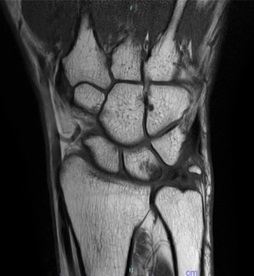

キーンベック病

誘因無く手関節が痛く力が入りにくくなる。XPで月状骨が破壊されてくる病気です。原因はわかりませんが、老人以外は進行してくることが多く積極的な治療が必要です。

治療方法

XP,MRIで病期を決定します。早期で橈骨が尺骨に比べて長い場合は橈骨短縮骨切り術、そうでない場合は当科では血管柄付き骨移植術を行っています。治療成績は非常に良好です。